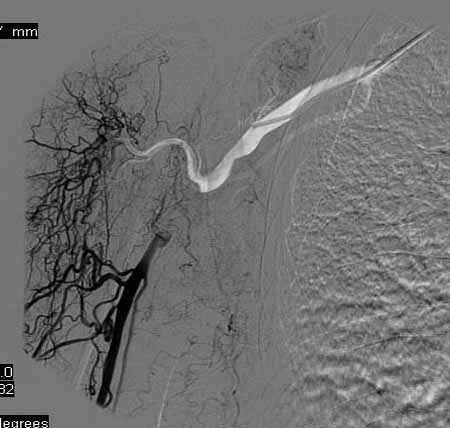

标题: DSA0091:肱动脉支架 [打印本页]

标题: DSA0091:肱动脉支架

女,66岁,右上肢无力.

馆主不错,图象清晰,栓塞处显示很清晰